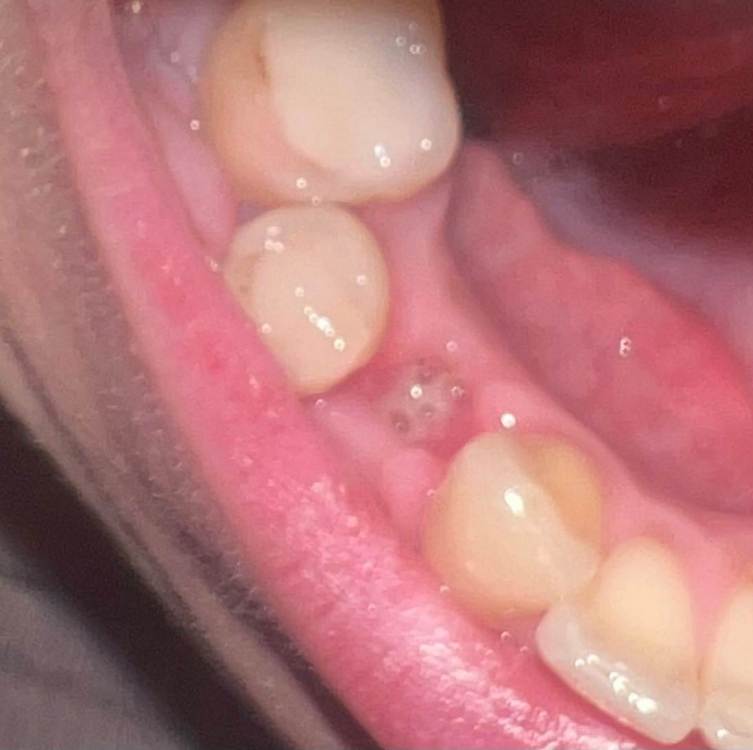

kruckovairina Опубликовано 6 июня, 2023 Автор Поделиться Опубликовано 6 июня, 2023 И десна с внешней стороны вот такая красная все это время после удаления не проходит Ссылка на комментарий